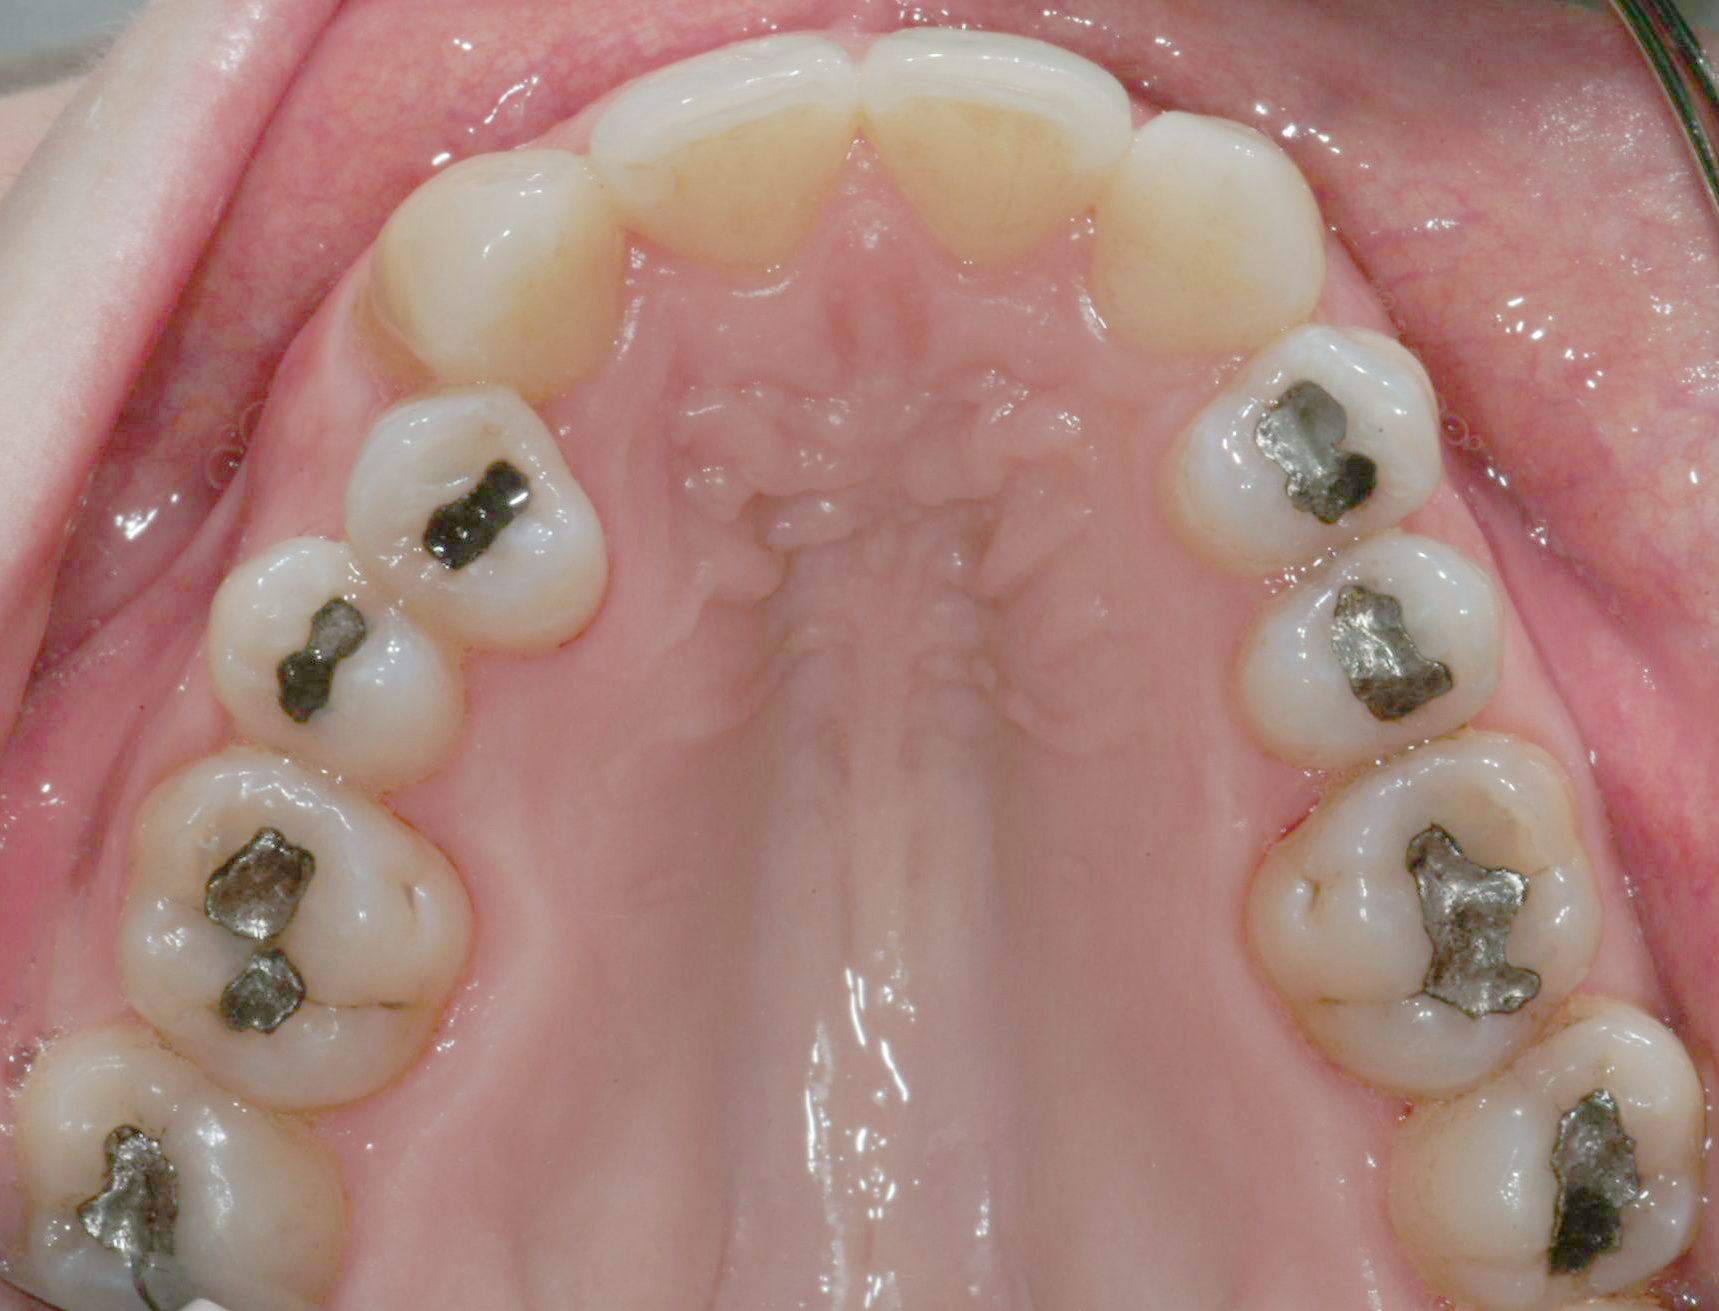

Per formulare corretta diagnosi e piano di cura, lo studio del caso ha previsto la raccolta di documentazione completa standard, ovvero fotografie del viso e intraorali (Figure 1a-e), radiografia panoramica e teleradiografia del cranio in proiezione laterale (Figure 2a-b) per la relativa analisi cefalometrica e modelli di studio.

Il protocollo terapeutico ha previsto l’estrazione del primo premolare inferiore sinistro (3.4) e del primo superiore destro (1.4), l’applicazione di una apparecchiatura fissa linguale 2D e di una meccanica asimmetrica di ancoraggio e movimento ortodontico a entrambe le arcate (Figure 3a-b).

Il trattamento è iniziato con l’estrazione dei due premolari in unica seduta in anestesia locale e l’applicazione simultanea, dopo una settimana, della apparecchiatura linguale inferiore e superiore, non essendoci problemi di overbite e potenziali interferenze in occlusione tra l’apparecchiatura superiore e i frontali inferiori. All’arcata superiore è stata effettuata una iniziale chiusura dello spazio estrattivo con forze molto leggere in ancoraggio medio su arco .014” Nichel-Titanio e successivamente .016” Nichel-Titanio, bondato in prima fase per maggior stabilità direttamente sulla superficie mesiale di 2.4.

In seguito, è stato modellato e applicato con tecnica adesiva diretta un pontic estetico in resina composita in sede 1.2, bondato sia distalmente a 1.1 sia mesialmente a 1.3, per un movimento en-masse in ancoraggio medio del gruppo frontale superiore, ottenuto nel settore 1 mediante forza elastica singola su arco .016” acciaio.

La rifinitura del caso ha previsto il completamento del livellamento del piano occlusale posteriore inferiore mediante meccanica cross-over con sezionali in acciaio .017”x .025” applicati sui primi e secondi molari e catenelle di derotazione tra i centrali superiori e tra 1.6 e 1.5 (Figure 8a-b).